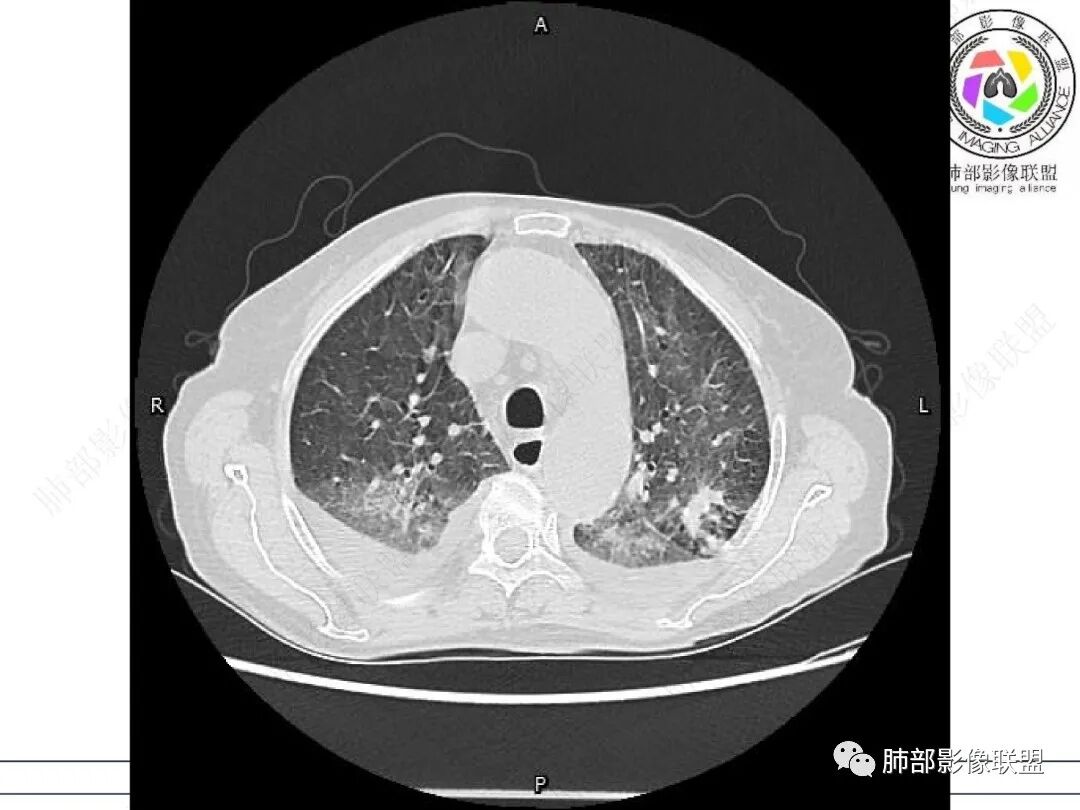

心脏大,胸腔积液,小叶间隔增厚,双肺磨玻璃影,考虑存在肺水肿,另双肺间质性炎性,类风关病史,考虑CTD-ILD,左肺上叶结核可能。

两肺叶后肋膈角区见多发蜂窝状结构破坏表现,双肺叶小叶间隔增厚,左肺上叶后段及舌段和右肺中叶胸膜炎性肉芽肿特点,双侧胸腔少量积液,有类风湿性关节炎治疗史,结缔组织相关性间质性肺病。

片状磨玻璃影,多发结节,类风湿肺炎?

发热,有类风湿性关节炎、糖尿病基础病,长期口服激素及免疫抑制剂,双肺多发磨玻璃影及小叶间隔增厚,蜂窝影,支气管扩张考虑非特异性间质性肺炎存在,左肺上叶不规则结节影,周围长毛刺局部肺气肿,考虑慢性炎症,结合pct及crp升高考虑细菌感染,另真菌g升高考虑结合宿主因素,真菌感染需要积极排除。

老年,外阴溃疡加发热,感染指标明显有异常,血气分析,过度呼吸及低氧血症,宿主因素,糖尿病和激素,基础疾病RA。影像,双下肺体积有缩小,有蜂窝?双肺磨玻璃,多发结节,双侧胸水。树芽不明确。是否有旧片,这个患者有UIP背景,是否感染或者UIP急性加重,或者基础上合并肺栓塞及肺水肿?长期激素,没有提供CD4细胞亚群,存在2种情况,1,风湿病没有压制住,肺考虑CTD相关性间质改变,压制过猛,结合感染指标,奴卡是有可能的。激素加糖尿病,结核也带排,激素加磨玻璃加G实验阳性,PCP也带排,临床信息太少,进一步排查

老年女性,有高血压糖尿病及类风湿性关节炎病史,发病前发烧。影像学两肺弥漫性磨玻璃影及斑片影,有渗出性病变亦有间质性改变,支气管血管束增粗,有牵拉扭曲有小气管扩张及间质增厚,两肺下叶胸膜下少许蜂蜜状影。两侧胸腔积液。考虑类风湿性关节炎肺内浸润?合并真菌感染?

老年女性,类风湿关节炎病史多年。发热。以两肺下叶为主弥漫磨玻璃及网格状透亮影,透亮度减低,局部小蜂窝状改变;两肺胸膜下散在几枚实性病灶;双侧胸腔积液。考虑RA-ILDNSIP

双下肺后肋膈角区见多发蜂窝,小叶间隔增厚,磨玻璃改变,,双侧胸腔少量积液,Crp明显升高,有类风湿性关节炎,糖尿病。甲氨蝶呤,托法替布治疗。会阴溃疡。考虑:1.免疫妥协2.pcp?巨细胞病毒?3.甲氨蝶呤致肺损伤?4.Ctd-ild.

类风湿病史,双肺小叶间隔增厚,散在磨玻璃密度增高影,双侧胸腔积液,患者免疫妥协,发热,PJP、病毒感染,类风湿相关性肺部改变

两下肺多发蜂窝状表现,双肺小叶间隔增厚,双肺磨玻璃影及部分炎性肉芽肿表现,双侧胸腔积液,有类风湿性关节炎治疗史,结缔组织相关性间质性肺病。患者C反应蛋白和降钙素原都高,是否合并细菌感染

女,71,外阴疼痛2周,发热1周。类风关、高血压、高血糖、卵巢囊肿、肠粘连、胆囊结石等病史及相关药物治疗史。胸部CT:两肺弥漫磨玻璃,血管束增粗,两下肺后肋膈角多发蜂窝,对称分布,双侧胸腔少量积液,纵隔窗心脏大血管影明显增宽。考虑混合性病变,CTD-ILD,并肺水肿?并PJP?。

①影像表现复杂:较弥漫间质性改变,对称磨玻璃密度为主,小叶间隔增厚,有一定重力分布趋势,未见明显纤维化,气囊及蜂窝位于肺边缘,未见典型“月弓征”。心脏影增大,双侧胸腔积液。

这即可见于间质性肺病,也可见于真菌感染(如PJP)、病毒感染,类风湿,以及肺水肿等等。

一般而言,如存在磨玻璃密度影浑浊,有重力分布趋势,肺表面蜂窝影,胸腔积液等等,并不常见于单纯PJP,除非其他因素叠加。